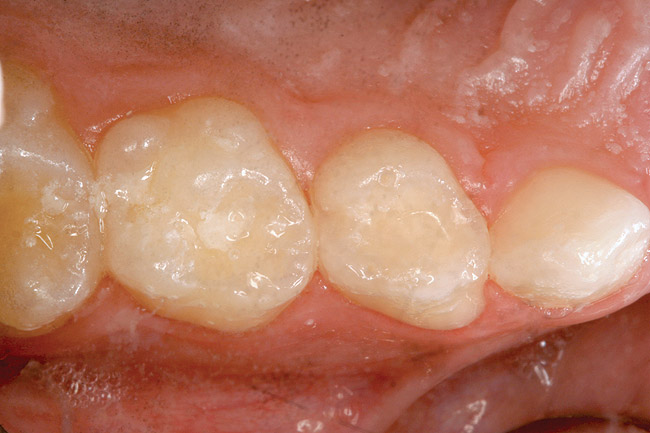

Figure 4  White spot lesions are imperceptible, blending with natural tooth color, after caries infiltration therapy (photograph courtesy of S. Paris and H. Meyer-Lueckel).

Figure 4

Caries infiltration is indicated for all age groups, up to the first third of dentin (D-1) (Figure 2). It is especially advantageous in interproximal areas, where a relatively large ratio of healthy hard tissue must be removed to eliminate carious tissue. Infiltration replaces hard tissue lost due to demineralization (to a maximum of 800 µm) with a low-viscosity resin, creating a barrier to further diffusion of carbohydrates and organic acids within the hard tissue, not on the tooth surface. This barrier stabilizes and effectively blocks the caries without changing the anatomic shape or appearance of the tooth.85 Additionally, treated lesions lose their whitish opaque color and blend with surrounding natural enamel, which is especially esthetic in the smooth surface type of lesions often found when fixed orthodontic appliances are removed (Figure 3 and Figure 4).